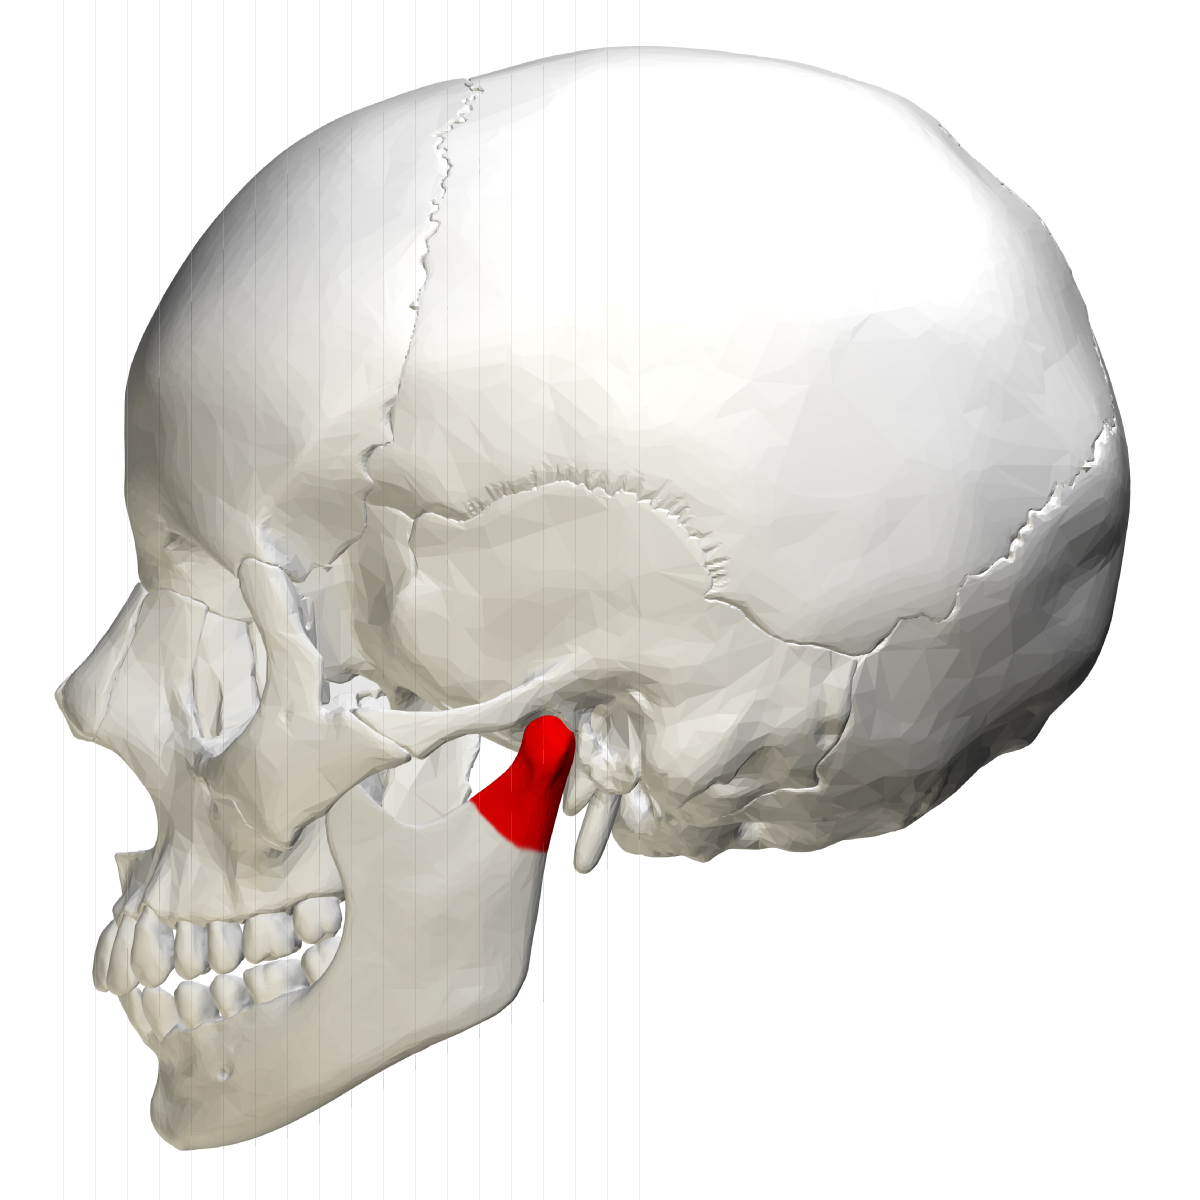

articular eminence

projection of temporal bone located anterior to glenoid fossa

rounded radiopaque projection of bone located anterior to glenoid fossa, not seen intraorally